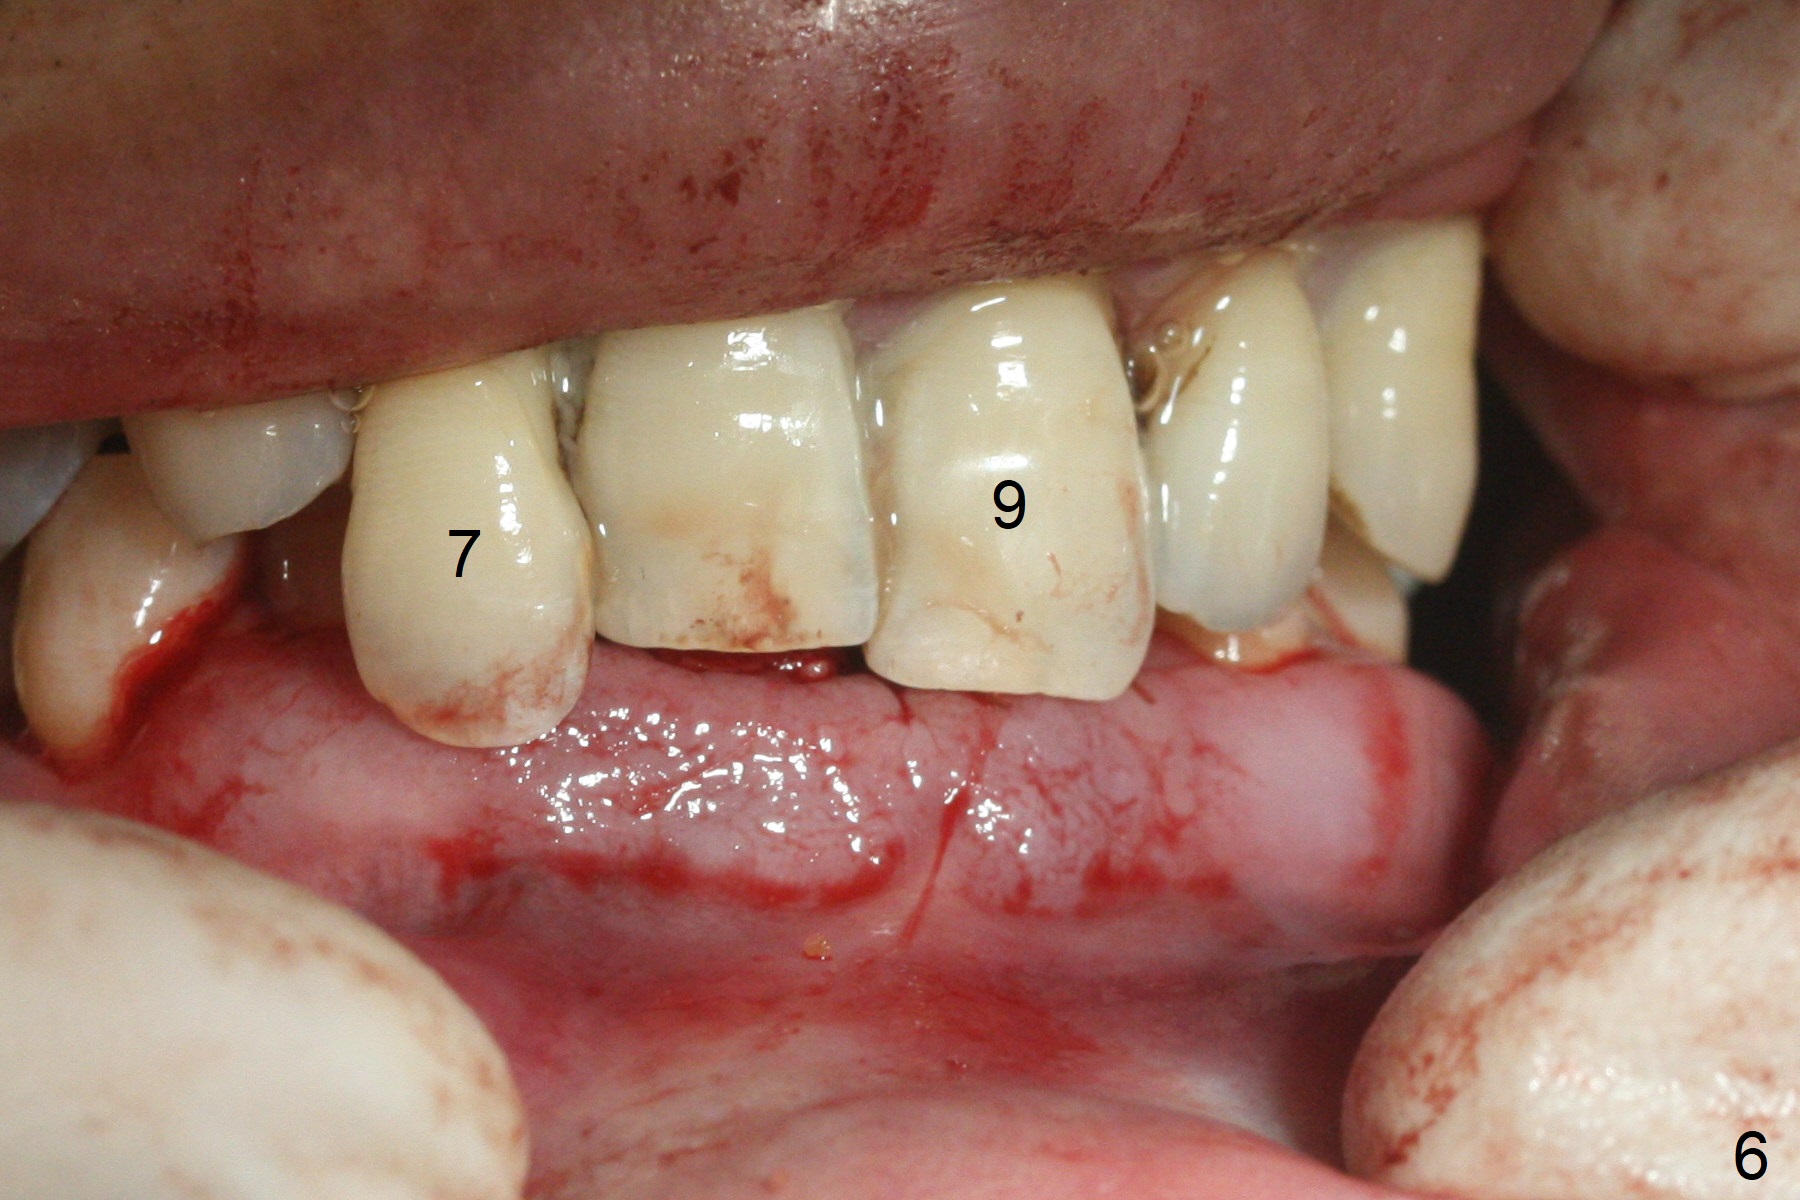

After extraction of 4 of the lower incisors, there are basically 2 sockets (#23/24 and 25/26), separated by the apparently midline bone (Fig.1 red line). In spite of using Lindamann bur to move the 25/26 osteotomy mesially, a 3x14(2) mm dummy implant remains close to the tooth #27 (Fig.2). The terminal branch of the Incisive Canal (<) is located between the lateral and central incisors. A de novo osteotomy (Fig.3 (1.5 mm drill)) is made mesial to the original one (O). While the 3x14(2) mm dummy implant is incompletely placed at #25/26, a 3x14(4) mm 1-piece one is placed at #23/24 (Fig.4). Finally the same implant is placed at #25/26 with placement of mineralized cortical/cancellous bone (Fig.5 *). When the large sockets are sutured, the supraerupted teeth #7-9 touch the lower gingiva (Fig.6). The incisal edge is reduced for clearance (Fig.7). Periodontal dressing is less likely to be dislodged with the incisal edge reduction (Fig.8,9). A provisional FPD is fabricated 1 week postop. Hard (Fig.10) and soft (Fig.11,12) tissues heal 5.5 months postop. The patient returns for crown cementation 3 months post impression (9 months postop, Fig.13,14).